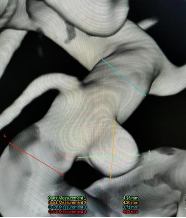

2020.07.03燕达医院

手术方案:支架辅助下右侧眼动脉段动脉瘤栓塞术

手术指征:眼动脉段动脉瘤(患者存在症状加重,上睑下垂考虑动脉瘤有增长趋势)

动脉瘤大小

此患者颈内—眼动脉瘤为宽颈动脉瘤,单纯弹簧圈栓塞有导致弹簧圈脱出或者栓塞不致密复发率高的可能,支架弹簧圈辅助栓塞是目前较为主流的介入治疗方式,Enterprise2支架是自膨式激光雕刻闭环支架,操作简单,精准定位,输送性佳,容易通过迂曲病变。

Enterprise2支架同1代支架相比,通过增加支架直径和正弦波几何结构的波幅,改善支架在弯曲血管中的贴壁性,在弯曲血管大弯侧避免支架丝突入瘤腔,更安全;在弯曲血管小弯侧无“鱼嘴效应”,致密栓塞率更高,同时增加了支架标记的可视性。